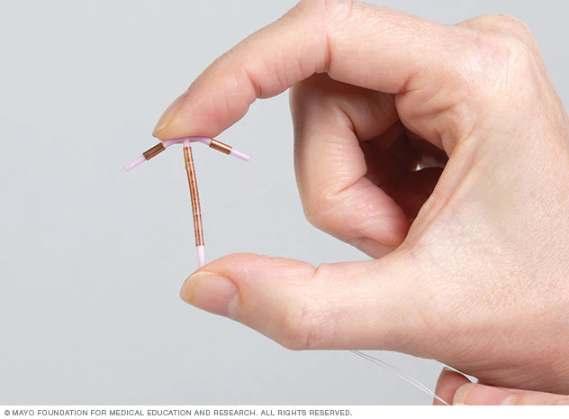

7.1.2. Dispositivos intrauterinos (DIU)

DISPOSITIVOS INTRAUTERINOS (DIU)

En la ventajas y desventajas del DIU hay más conceso que sobre otros métodos, las ventajas se refieren a su efecto a largo plazo, es duradero y muy efectivo, no interfiere en las relaciones sexuales, reversible y que ayude prevenir el embarazo ectópico.

Sin embargo, es importante discutir con un médico o profesional de la salud para determinar si es el método anticonceptivo adecuado para ti, considerando tus necesidades y circunstancias personales.pélvicas o riesgo de ETS.

Mientas que en las desventajas están los cambios menstruales y que está contraindicado cuando hay antecedentes de enfermedades inflamatorias Los DIU son una opción popular para muchas mujeres debido a su alta eficacia y conveniencia.